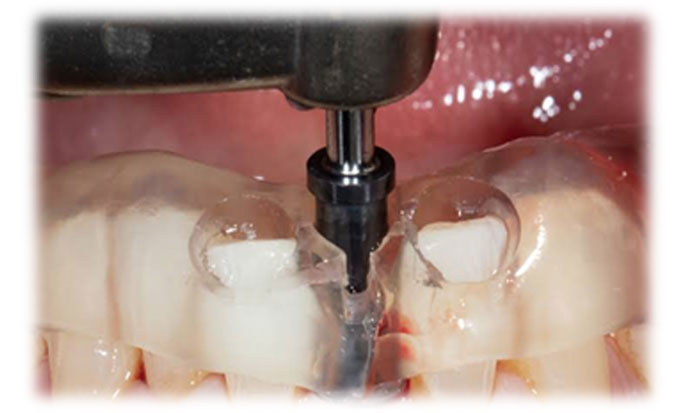

Guided Implant Surgery involves the use of advanced 3D imaging and computer-aided design (CAD) to plan the exact placement of dental implants. This meticulous planning process allows our dental specialists to visualize the patient’s oral anatomy in great detail, ensuring the implants are placed in the most ideal position for both functionality and aesthetics. The procedure is tailored to each patient's unique needs, ensuring a personalized treatment plan.

These technique assures that the implant is precisely placed without any damage to nerves, vessels and wouldn't perforate maxillary sinus too.